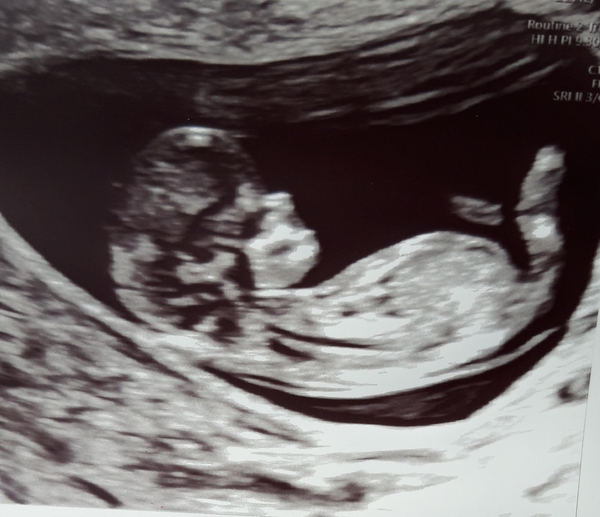

blackpinkinyourarea · 22/01/2020 19:59

I had my 12 week scan today, my new EDD is August 9th so Im 11 weeks and 3 days today.

This morning did not get off to the best start however. As soon as I got out of bed, I started absolutely gushing red blood! No clots and no pain, it was just a torrent of it and it then stopped very abruptly. I tried to not freak out too much as I knew I had a scan literally 3 hours later but was still terrified. Long story short, the baby is doing well and looked very active and healthy during the scan! There was no identifiable cause of the bleed. Im so relieved, but also worried that something could still end up going wrong :(

DanielleG96 · 23/01/2020 12:45

Hi everyone had my 12 week scan this morning. Baby is measuring 12 weeks and 2 days so exactly where I thought I would be with due date being 4th August. Very wriggly and had its hand on its face the whole time but very cute!

MaisieMolly · 23/01/2020 13:13

Hi ladies, I had my scan today as well! I’m 12 weeks exactly and all is well so far. What a relief!

PandaPink · 24/01/2020 07:38

Totally forgot to post this yesterday. 12 week scan at which I though I was 11+6 I have been measured at 12+5!! I am spot on with my dates though so baby is growing rapidly. Due date now 1st August.

I will have extra growth scans every 4 weeks where they will plot a chart of the growth.

Baby was jumping around all over the place so they couldn't measure fluid at the back of the neck.

I'm so pleased though Smile